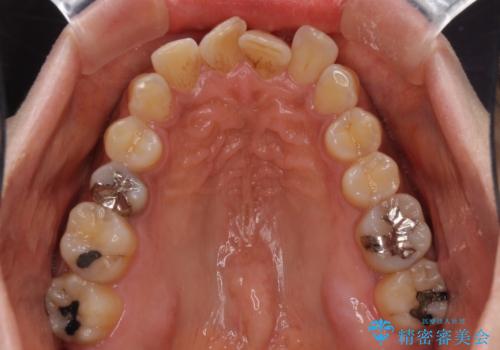

- 40代女性

- インビザライン

- 上下前歯のデコボコ改善をインビザラインにて行いたいとのことで来院された患者様です。

インビザラインをご希望のことで、IPR(歯と歯の間を削る)などによりスペースを獲得して、排列していくこととしました。

骨格的に上下顎が左右にずれていたため、正中位置は現状を維持したまま歯列不正を解消していくことになります。

なかなか装着時間が守れず、後戻りを繰り返しながら治療を進めたため、インビザライン治療期間期限ギリギリの5年弱の期間を要しました。